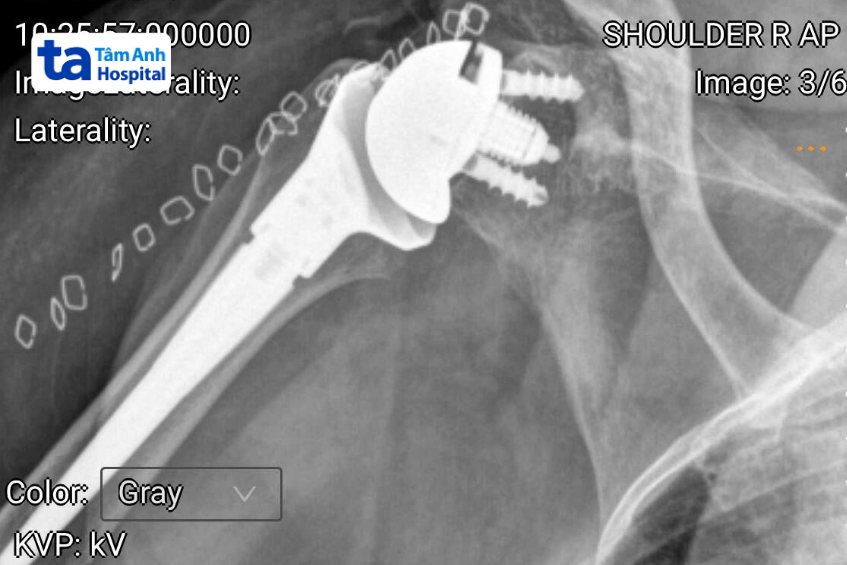

Sau điều trị nội khoa, bác sĩ tiến hành thay khớp vai nhân tạo cho bà Kiều bằng phương pháp tiếp cận lối trước qua đường delta ngực (đi giữa cơ ngực và cơ delta) với đường mổ khoảng 8-10 cm. Với kỹ thuật này, bác sĩ tiếp cận khớp vai mà không cần cắt cơ, hạn chế tổn thương mạch máu thần kinh.

Nhờ đó, người bệnh ít đau, ít mất máu, có thể sớm tập phục hồi chức năng sau phẫu thuật. Các gân cơ chóp xoay bị rách cũng được khâu nối lại, nhất là gân cơ dưới vai, nhằm giữ vững và tránh nguy cơ trật khớp vai ra trước, một trong những biến chứng phổ biến của thay khớp vai. Ca mổ kết thúc sau hơn 45 phút.

Ngày đầu tiên sau phẫu thuật, người bệnh cho biết giảm đau đáng kể, có thể đưa tay ra trước khoảng 90 độ, tình trạng phục hồi tốt và được xuất viện. bà Kiều cần đeo đai trong 4 tuần để phần gân cơ được khâu lại có thể lành tốt nhất. Dự kiến sau 2 – 3 tháng tập vật lý trị liệu, người bệnh có thể sinh hoạt gần như bình thường.